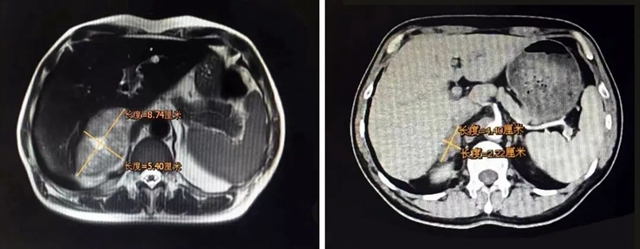

2018年11月,肾上腺转移瘤体积缩小了80%,腰部胀痛消失、体重逐渐增加,身体体质得到明显改善。

治疗前(左);治疗后(右)